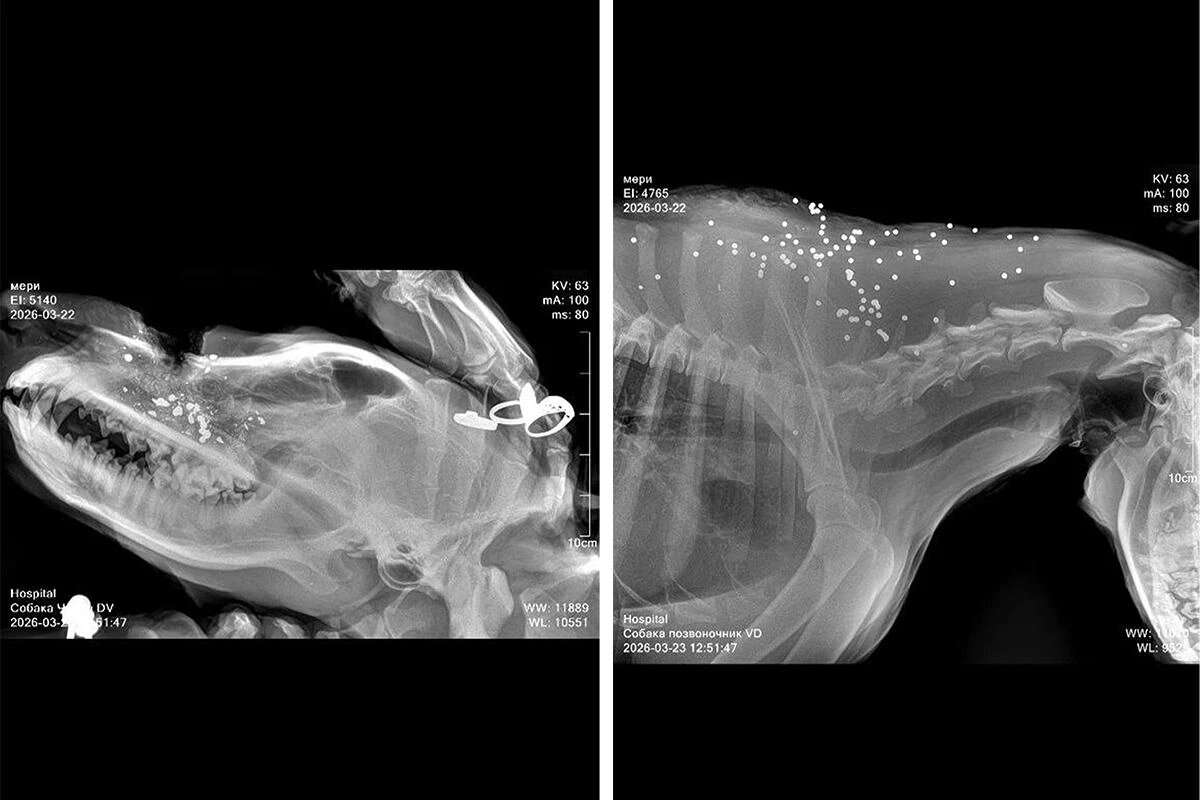

По утверждению очевидцев, животные были расстреляны из дробовика. В результате нападения одна собака погибла, пострадали еще как минимум три. Двое пострадавших животных убежали, а третье экстренно доставили в ветеринарную клинику. У собаки огнестрельные ранения дробью, за ее жизнь борются врачи.